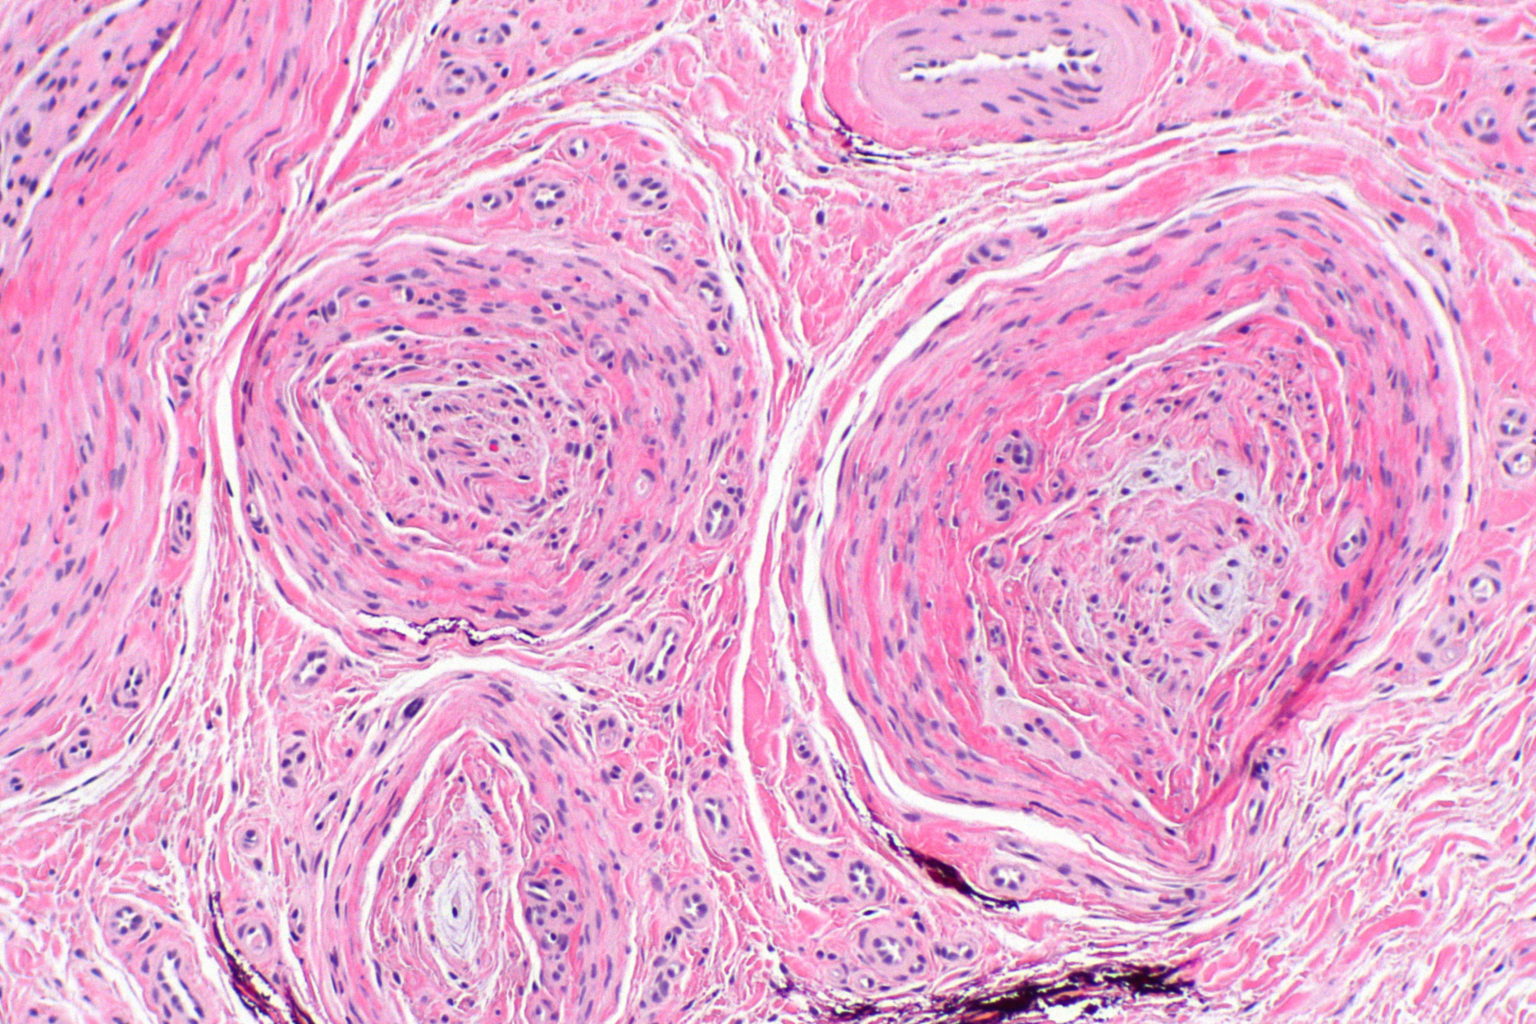

From www.cureus.com

Development of Traumatic Neuromas in a Patient Following Endovenous Laser For Neuroma using exclusive laser treatment, a foot neuroma case (for a patient that was not effectively treated by conventional medicine). the treatment goals for morton's neuroma are to minimise pain and improve function. laser therapy, with its proven efficacy and minimal side effects, has emerged as a superior alternative for. some imaging tests are more useful than. Laser For Neuroma.